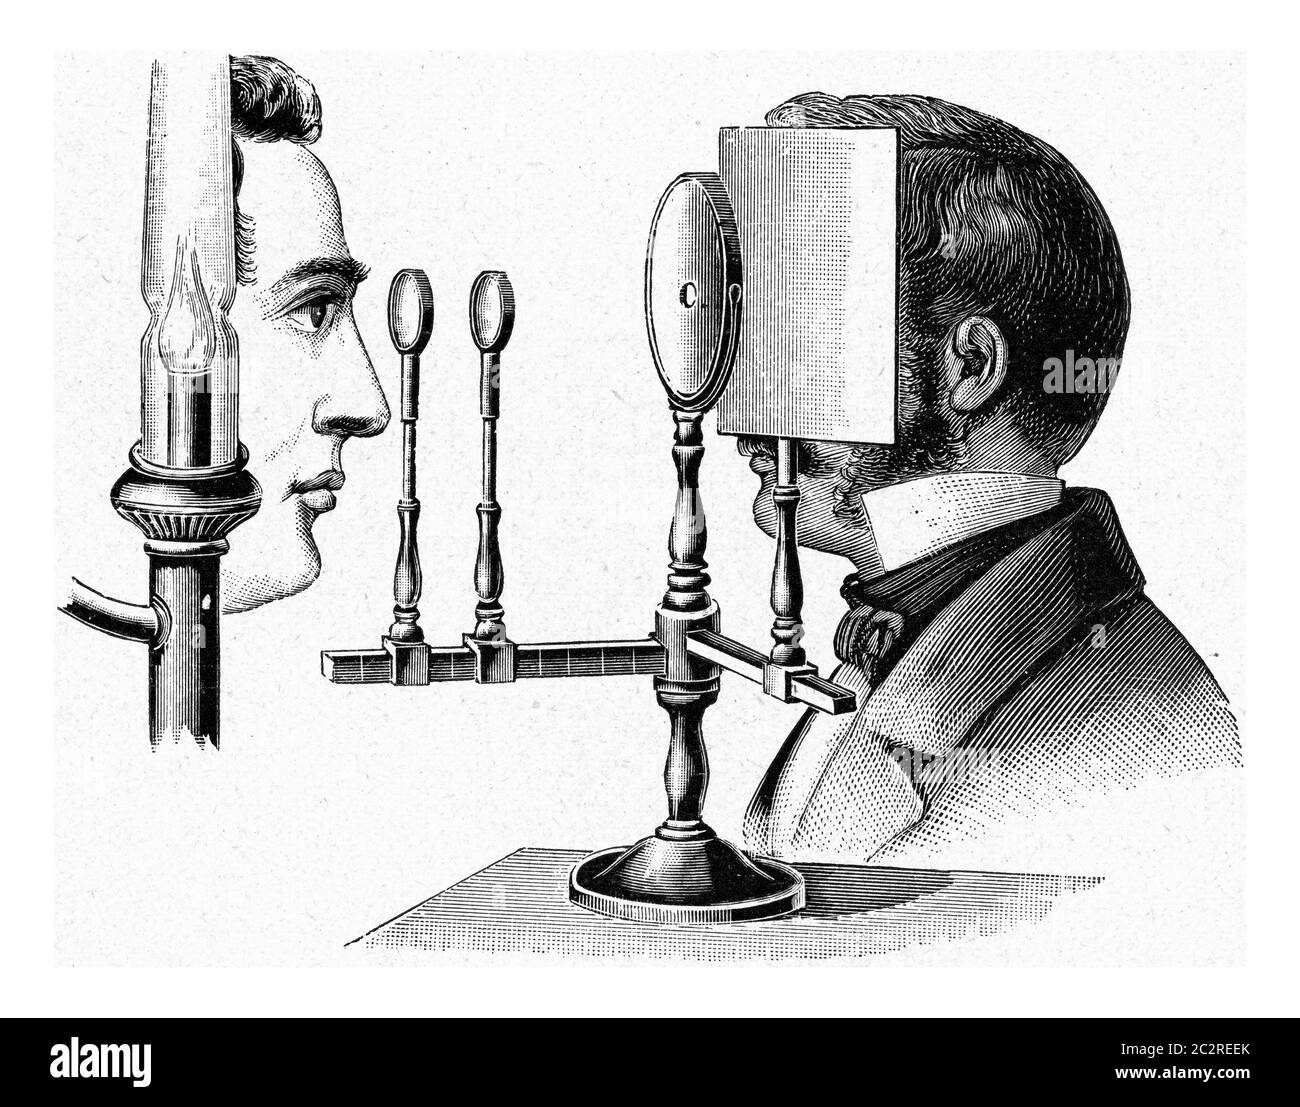

Engraving depicting an ophthalmoscope in use. Ophthalmoscopy, also called funduscopy, is a test that allows a health professional to see inside the fundus of the eye and other structures. The ophthalmoscope was invented by Hermann von Helmholtz (1821-1894) a German physician and physicist. Dated 19th century Stock Photohttps://www.alamy.com/image-license-details/?v=1https://www.alamy.com/engraving-depicting-an-ophthalmoscope-in-use-ophthalmoscopy-also-called-funduscopy-is-a-test-that-allows-a-health-professional-to-see-inside-the-fundus-of-the-eye-and-other-structures-the-ophthalmoscope-was-invented-by-hermann-von-helmholtz-1821-1894-a-german-physician-and-physicist-dated-19th-century-image186347727.html

Engraving depicting an ophthalmoscope in use. Ophthalmoscopy, also called funduscopy, is a test that allows a health professional to see inside the fundus of the eye and other structures. The ophthalmoscope was invented by Hermann von Helmholtz (1821-1894) a German physician and physicist. Dated 19th century Stock Photohttps://www.alamy.com/image-license-details/?v=1https://www.alamy.com/engraving-depicting-an-ophthalmoscope-in-use-ophthalmoscopy-also-called-funduscopy-is-a-test-that-allows-a-health-professional-to-see-inside-the-fundus-of-the-eye-and-other-structures-the-ophthalmoscope-was-invented-by-hermann-von-helmholtz-1821-1894-a-german-physician-and-physicist-dated-19th-century-image186347727.htmlRMMR4TBY–Engraving depicting an ophthalmoscope in use. Ophthalmoscopy, also called funduscopy, is a test that allows a health professional to see inside the fundus of the eye and other structures. The ophthalmoscope was invented by Hermann von Helmholtz (1821-1894) a German physician and physicist. Dated 19th century

An old engraving of an ophthalmoscope. It is from a Victorian book of the 1880s. Ophthalmoscopy (or funduscopy) allows a doctor to see inside the eye using this device. This version is Knapp’s auto-ophthalmoscope, set up in front of a patient. A light source (a) supplies light to an inclined reflector (b) which bounces the light towards the patient’s pupil (c in the top diagram). A hole in the plate at the rear of the instrument allows the doctor to view (d). The ophthalmoscope was invented by Hermann von Helmholtz in 1851. Hermann Knapp of New York was an expert instrument and lens maker. Stock Photohttps://www.alamy.com/image-license-details/?v=1https://www.alamy.com/an-old-engraving-of-an-ophthalmoscope-it-is-from-a-victorian-book-of-the-1880s-ophthalmoscopy-or-funduscopy-allows-a-doctor-to-see-inside-the-eye-using-this-device-this-version-is-knapps-auto-ophthalmoscope-set-up-in-front-of-a-patient-a-light-source-a-supplies-light-to-an-inclined-reflector-b-which-bounces-the-light-towards-the-patients-pupil-c-in-the-top-diagram-a-hole-in-the-plate-at-the-rear-of-the-instrument-allows-the-doctor-to-view-d-the-ophthalmoscope-was-invented-by-hermann-von-helmholtz-in-1851-hermann-knapp-of-new-york-was-an-expert-instrument-and-lens-maker-image386693636.html

An old engraving of an ophthalmoscope. It is from a Victorian book of the 1880s. Ophthalmoscopy (or funduscopy) allows a doctor to see inside the eye using this device. This version is Knapp’s auto-ophthalmoscope, set up in front of a patient. A light source (a) supplies light to an inclined reflector (b) which bounces the light towards the patient’s pupil (c in the top diagram). A hole in the plate at the rear of the instrument allows the doctor to view (d). The ophthalmoscope was invented by Hermann von Helmholtz in 1851. Hermann Knapp of New York was an expert instrument and lens maker. Stock Photohttps://www.alamy.com/image-license-details/?v=1https://www.alamy.com/an-old-engraving-of-an-ophthalmoscope-it-is-from-a-victorian-book-of-the-1880s-ophthalmoscopy-or-funduscopy-allows-a-doctor-to-see-inside-the-eye-using-this-device-this-version-is-knapps-auto-ophthalmoscope-set-up-in-front-of-a-patient-a-light-source-a-supplies-light-to-an-inclined-reflector-b-which-bounces-the-light-towards-the-patients-pupil-c-in-the-top-diagram-a-hole-in-the-plate-at-the-rear-of-the-instrument-allows-the-doctor-to-view-d-the-ophthalmoscope-was-invented-by-hermann-von-helmholtz-in-1851-hermann-knapp-of-new-york-was-an-expert-instrument-and-lens-maker-image386693636.htmlRM2DD3BK0–An old engraving of an ophthalmoscope. It is from a Victorian book of the 1880s. Ophthalmoscopy (or funduscopy) allows a doctor to see inside the eye using this device. This version is Knapp’s auto-ophthalmoscope, set up in front of a patient. A light source (a) supplies light to an inclined reflector (b) which bounces the light towards the patient’s pupil (c in the top diagram). A hole in the plate at the rear of the instrument allows the doctor to view (d). The ophthalmoscope was invented by Hermann von Helmholtz in 1851. Hermann Knapp of New York was an expert instrument and lens maker.